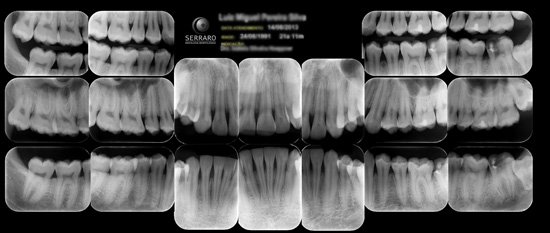

Exame radiográfico periapical completo das arcadas. São realizadas um total de 14 radiografias periapicais, assim dispostas: Molares, pré-molares, caninos e incisivos, em ambos os lados e arcadas.

14 periapicais, 4 interproximais e radiografia panorâmica)

Exame composto de uma tomada radiográfica panorâmica, periapicais boca toda e interproximais de molares e pré-molares. Alia a amplitude de visualização da panorâmica associada com a riqueza de detalhes obtidas nas radiografias periapicais e interproximais que somada a um exame clínico minucioso permite um diagnóstico clínico mais preciso.